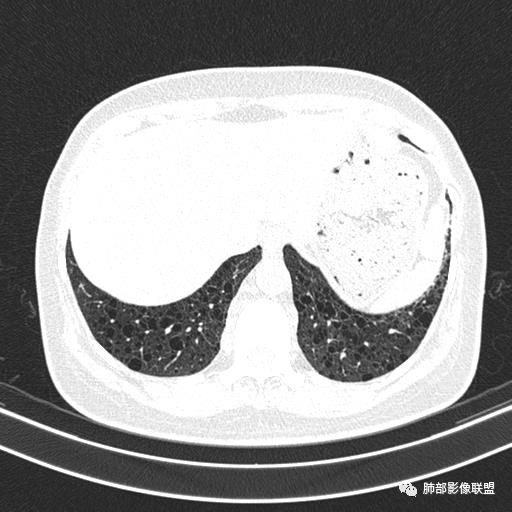

女,46,活动性气喘1年。苯吸入史半年。胸部CT:两肺弥漫囊腔,上至肺尖,下至肋膈角,形态类似小囊腔。考虑:LAM,鉴别LIP,BHD,PLCH等。

双肺弥漫大小不一薄壁含气囊腔,囊间肺组织正常,正常肺背景,肺尖肺底受累;青年女性,气喘,支持LAM

CT表现:双肺弥漫大小不等的薄壁囊腔,囊壁<2mm,外形规则,血管影多位于囊腔周围,囊腔之间肺组织正常,随着疾病进展到晚期,囊腔变大、增多,不可胜数,囊腔可融合成较大的囊,与肺气肿相似,形成间质性肺纤维化。部分病例可出现结节影。

临床诊断BHD综合征需要满足一个主要或两个次要标准。主要标准包括:1、皮肤上至少发现5个纤维滤泡瘤,至少1个组织学证实;2、致病的FLCN种系突变阳性。次要标准:1、多发肺囊肿,双侧基底部,有或无自发性气胸;2、肾癌,起病早(<50岁)或多灶性或双侧;3、 BHD综合征一级亲属。BHD主要影像表现特征:1、两肺内肺囊肿:80%以上的BHD患者会出现肺内囊肿,且倾向于基底部近胸膜下分布,特别是纵膈侧肺膜下,囊肿形状不规则、囊肿可大可小,肺内囊肿多毗邻肺下动脉或静脉近端,胸部CT上囊肿分布和特点对诊断有提示意义。2、继发自发性气胸:BHD患者发生气胸风险是正常人的5倍,BHD患者的气胸发生率约为 1/4,气胸复发率则高达59%。3、肾肿瘤:(常为双侧性、倾向于嫌色细胞组织学亚型)4、皮肤表现(为面、颈部纤维性毛囊瘤、毛盘瘤)